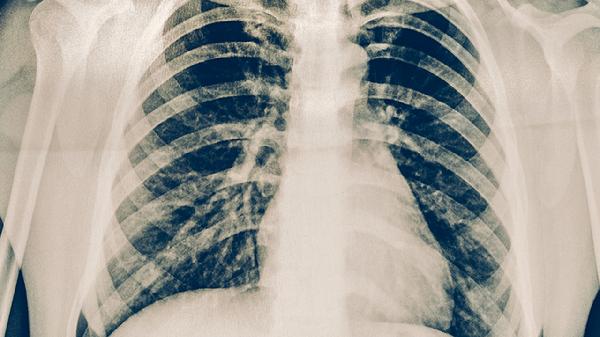

轻症患者呼吸道黏膜损伤较轻,免疫细胞再生速度较快,通常2周内可恢复免疫功能;中重度感染可能引发持续性炎症反应,需3-4周才能重建免疫屏障。合并肺外并发症者恢复期可能延长。